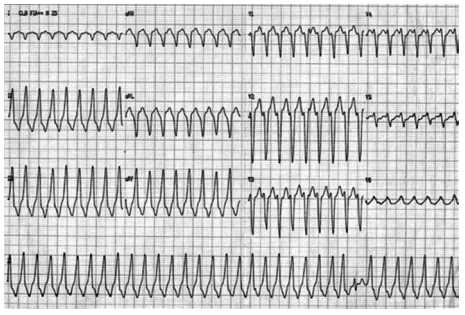

Homem, 82 anos, procura unidade básica de saúde próximo à sua residência com queixa de náuseas, vômitos e dor retroesternal de forte intensidade irradiada para membro superior esquerdo, associada a sudorese de início há 2 horas. Refere ser hipertenso, diabético e ex-tabagista. Faz uso de insulina NPH, losartana, metformina e sinvastatina. Exame físico: regular estado geral, pálido, sudoreico, PA = 80x60 mmHg, FR = 18 ipm, estase jugular bilateral. Ausculta cardíaca: bulhas rítmicas normofonéticas sem sopros; ausculta pulmonar: murmúrio vesicular presente e simétrico sem ruídos adventícios. O eletrocardiograma realizado na admissão está ilustrado a seguir.

No atendimento inicial desse paciente, além da administração de AAS e da pronta remoção para serviço habilitado para reperfusão coronária, o paciente deve receber prontamente